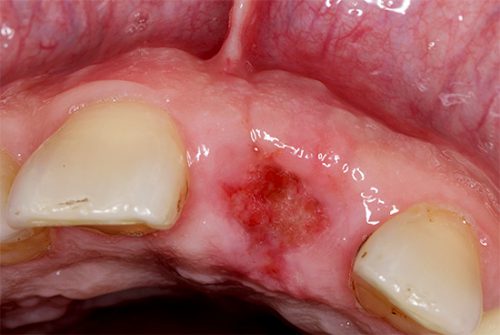

- В течение суток наблюдается усиление болевой реакции и отечность мягких тканей. Раневая поверхность покрыта плотным сгустком крови. На третьи сутки появляются первые признаки восстановления эпителия.

- Через неделю кровяной сгусток изменяется в цвете и начинает замещаться на грануляции. Обновленный эпителий формируется по периферии раны. В центре еще есть остатки сгустка.

- На 15 день эпителий полностью закрывает проблемную зону. Появляются первые признаки формирования костной ткани.

- К 20 дню происходит полное созревание эпителия. Грануляционная ткань начинает резорбцироваться. Наблюдается заживление раны после удаления зуба с проявлением остеогенеза.

- Через месяц отмечается активный рост костной ткани по краям раны по направлению к центру. Грануляции к этому времени практически полностью отсутствуют.

- Спустя 2-3 месяца лунка заполняется новыми костными элементами. Однако ее признаки еще определяется визуально.

К четырем месяцам происходит полное восстановление. Но гребень альвеолярного отростка в этой области будет иметь низкий уровень по сравнению с другими участками челюсти.